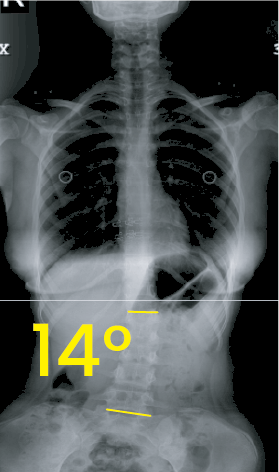

Göğüs bölgesinde 14 derece eğrilik gösteren omurga röntgeni görüntüsü.Göğüs ve karın bölgesini içeren, omurgada 1 derece eğrilik gösteren frontal X-ışını görüntüsü.

Toraks röntgen görüntüsünde 30 derecelik skolyoz eğriliği sarı açılarla ve beyaz çizgilerle işaretlenmiş.Göğüs ve bel bölgesini gösteren röntgen, omurga eğriliğinin 14 derece olduğunu belirtir.